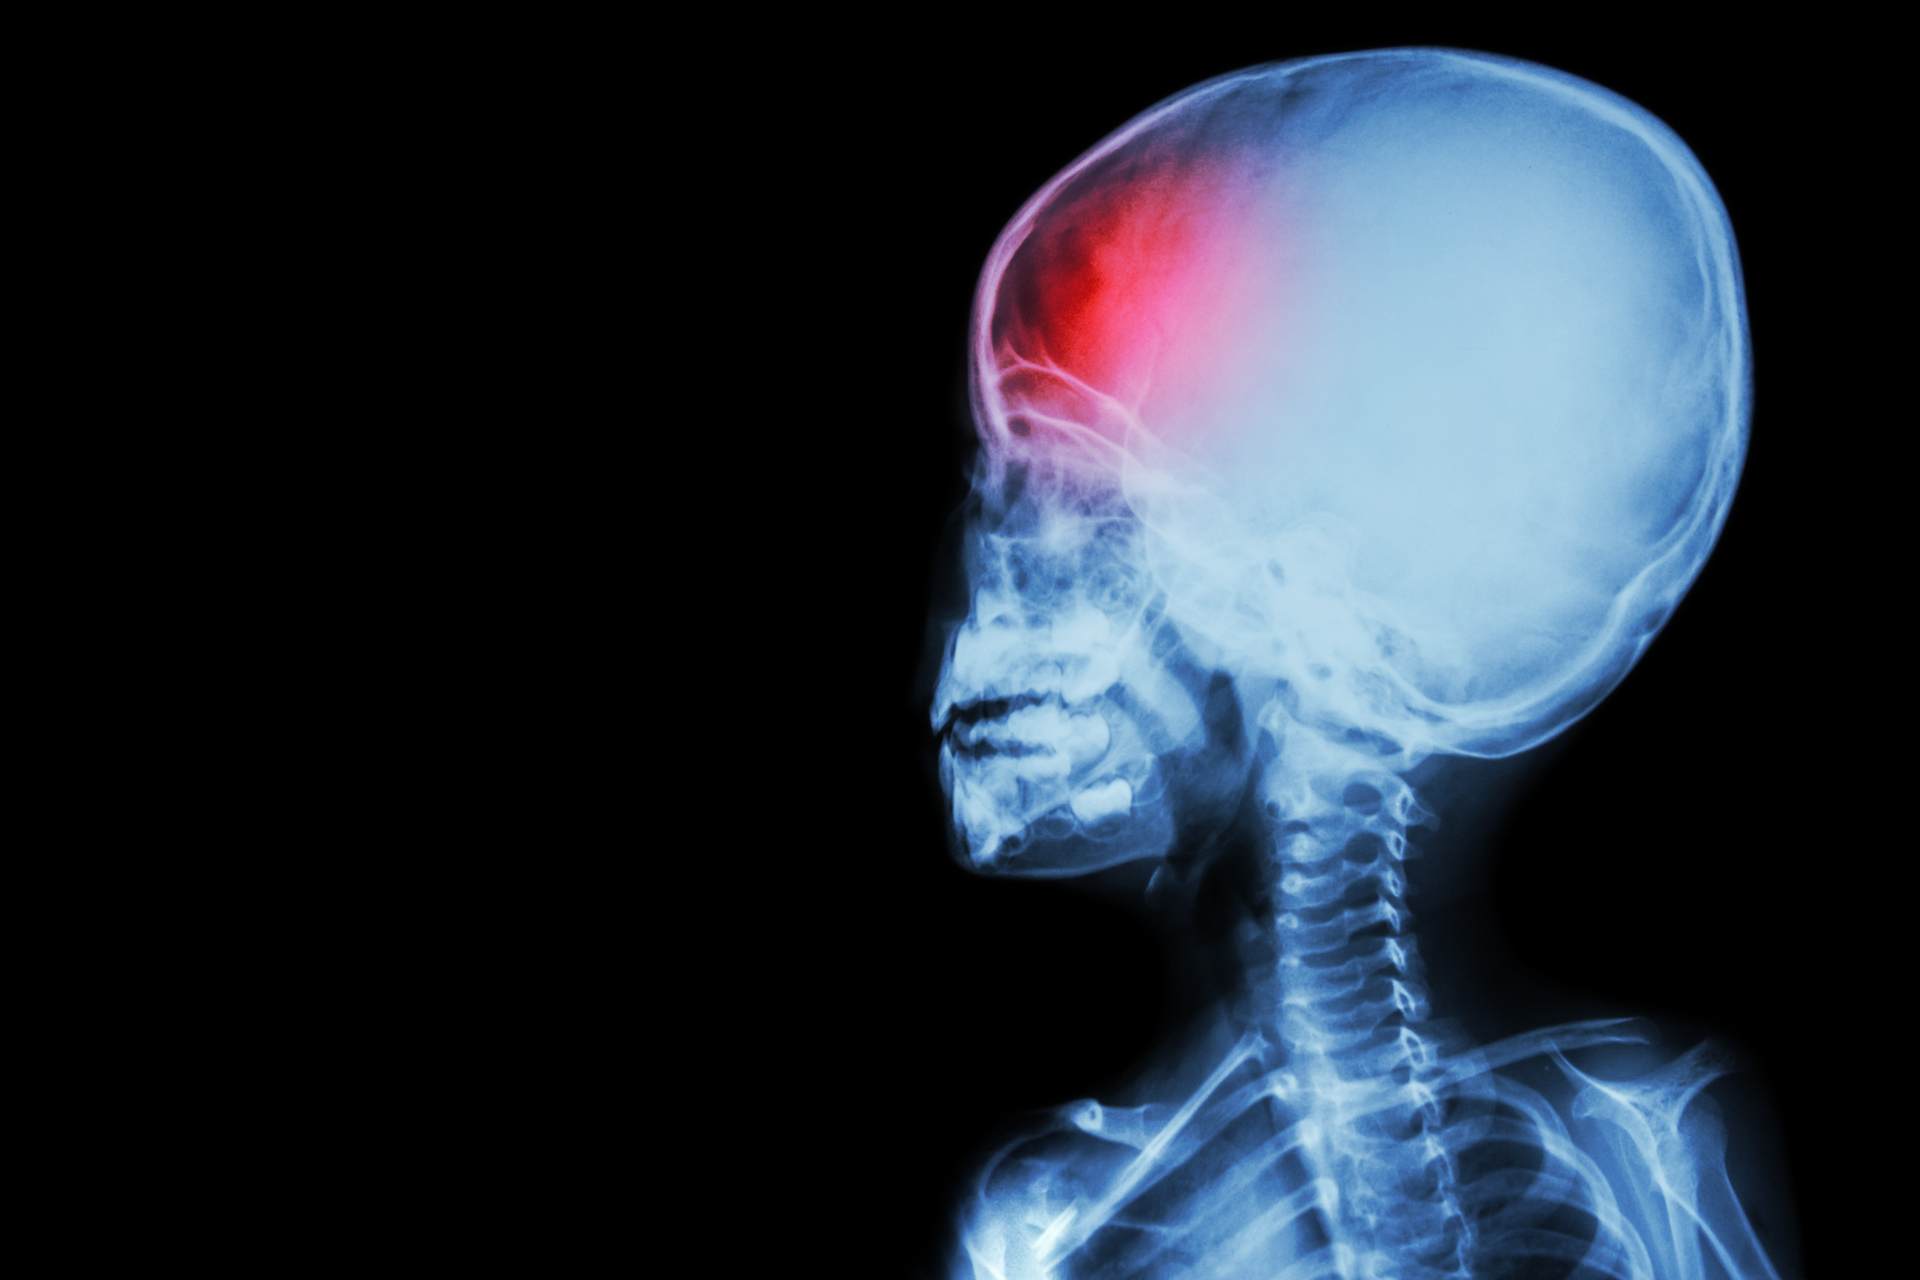

Study shows ketamine could be beneficial for treating brain injury in children

A common anesthesia drug could be beneficial in reducing pressure inside the skull of children with traumatic brain injuries (TBI), according to a study published in Critical Care Medicine.

Ketamine, a drug that has been used for anesthesia since the 1970s, has traditionally been avoided for patients with TBI due to early studies suggesting that it could raise the pressure inside of the skull, known as intracranial pressure (ICP).